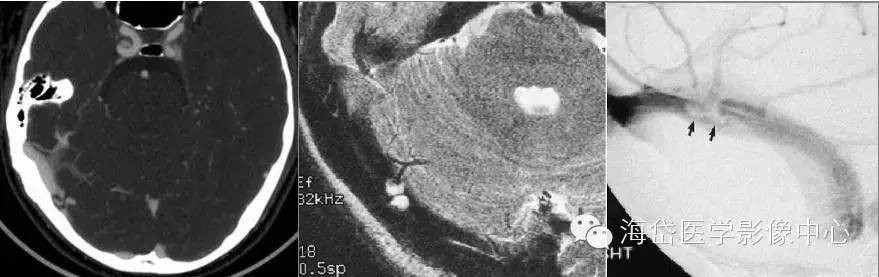

与静脉窦血栓鉴别

静脉窦血栓表现为静脉窦内充盈缺损,边界不规则;范围较广,可累及相邻静脉窦、浅表皮层静脉,甚至大脑深静脉,伴所在静脉窦扩张,静脉窦壁侧支循环;血栓信号类似于血肿随时间变化而变化;脑实质内可见静脉性水肿或出血。

蛛网膜颗粒表现为静脉窦内局限性充盈缺损,圆形或半圆形,边界规则;其所在静脉窦不扩张,大多数与脑脊液等信号或等密度;常位于静脉汇入静脉窦处,见静脉直接进入蛛网膜颗粒。